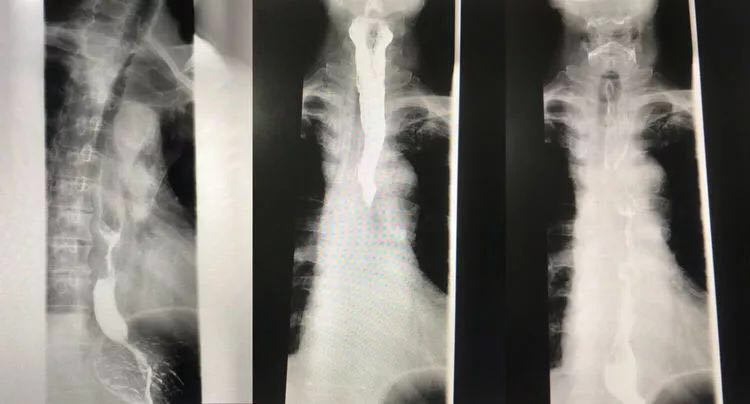

梅某,男,75岁,以吞咽不适20天为主诉入住我院,患者20天前无明显诱因出现吞咽不适症,无明显加重或缓解因素,伴有反酸,打嗝,胸痛等不适。就诊于当地某人民医院行胃镜检查:据门齿31cm处可见一新生物,病理活检:食管鳞癌。未给予治疗,为进一步治疗,门诊以"食管恶性肿瘤"为诊断入院。自发病以来,食欲可,精神可,大小便正常,体重无减轻。

3月15日在局麻下行冠状动脉造影术。冠状动脉造影术显示:LM(左主干):无明显狭窄,LAD(左前降至):近段70%狭窄,中段80%狭窄,D开口90%狭窄,LCX(左回旋支):无明显狭窄,RCA(右冠):近段70%狭窄。

科主任杨光煜及副主任胡为才考虑患者心脏,冠脉功能差,常规行胸腹腔镜联合食管癌根治术风险大,常规开胸手术风险高,为保证肿瘤根治性切除的目的,  请心内科,麻醉科及手术室多学科联合会诊讨论:一致决定行最新技术(微创):于3月19号全麻行"单孔充气式纵隔镜联合腹腔镜食管癌根治术"。优点:作为一种全新的充气式纵隔镜技术使手术视野十分清哳、大大提高了手术安全性、淋结清扫彻底、同时使食管全“系膜”切除(en bloc resection)成为可能,完全可以满足食管癌根治的肿瘤学要求,此类不进胸手术达到了让食管癌根治术更加微创化的目的大大降低心肺并发症的发生率,同时达到了让食管癌根治术更加微创化。手术历经7个小时,非常成功,术后仅有颈部一个切口,腹部5个1x1cm微创切口,患者术后顺利转入ICU。